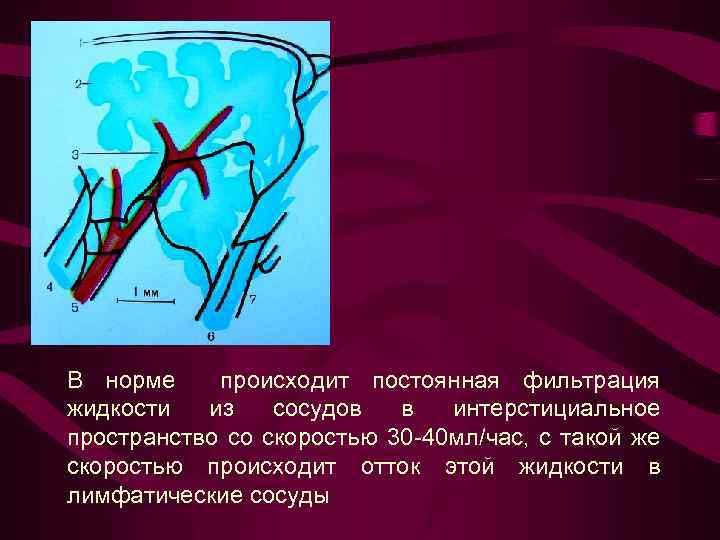

В норме происходит постоянная фильтрация жидкости из сосудов в интерстициальное пространство со скоростью 30 -40 мл/час, с такой же скоростью происходит отток этой жидкости в лимфатические сосуды

В норме происходит постоянная фильтрация жидкости из сосудов в интерстициальное пространство со скоростью 30 -40 мл/час, с такой же скоростью происходит отток этой жидкости в лимфатические сосуды